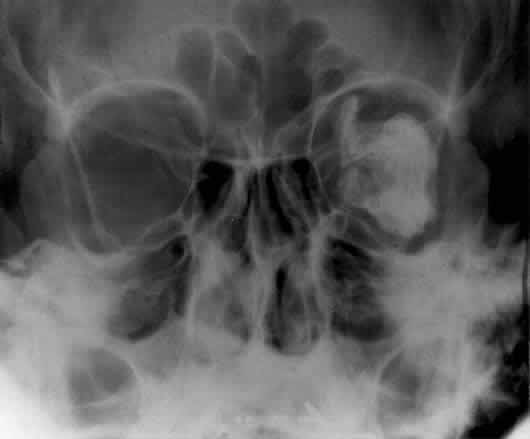

WATERS PROJECTION

In an attempt to improve the visualization of the maxillary and ethmoid sinuses, in 1915 Waters and Waldron7 described a radiographic projection (Fig. 2) that eliminated the overlapping shadows of the dense petrous ridge of the temporal bone. Waters projection is created by placing the chin of the patient on the x-ray cassette with the canthomeatal line (the line that connects the lateral canthus and the external auditory meatus) at 37 degrees to 45 degrees.5,6 This orientation is accomplished if the nose of the patient is approximately 0.5 to 1.5 cm above the x-ray plate.7,8 A mnemonic is—the patient raises the chin up to sip water.

Fig. 2. A. Schematic showing positioning for a Waters projection. (CM, canthomeatal line; CR, central ray) B. Radiograph of a Waters projection. The petrous ridge lies below the maxillary sinus. (a, frontal sinus; b, medial orbital wall; c, innominate line; d, inferior orbital rim; e, orbital floor; f, maxillary antrum; g, superior orbital fissure; h, zygomatic-frontal suture; i, zygomatic arch) (A; Rao VM, Gonzalez CF: Plain film radiography and polytomography of the orbit. In Gonzalez CF, Becker MH, Flanagan JC [eds]: Diagnostic Imaging in Ophthalmology, pp 1–7. New York, Springer Verlag, 1986)

Waters view provides the best image of the maxillary antrum and good images of the orbital rim, orbital floor, zygomatic bones and arches, lesser wing of the sphenoid, and infraorbital foramen. This view is useful to the clinician in orbital floor fracture assessment because of the clear image of the orbital floor and the underlying maxillary sinus. The floor of the orbit should form a continuous radiographic line with the lateral wall of the orbit. Confusion can occur regarding the location of the orbital floor and its relationship to the orbital rim. The orbital floor is located inferior to the orbital rim not in the same plane, because of the orientation of the patient's head in Waters projection. A soft tissue density in the roof of the maxillary sinus or opacification of the floor of the sinus suggests an orbital floor disruption.